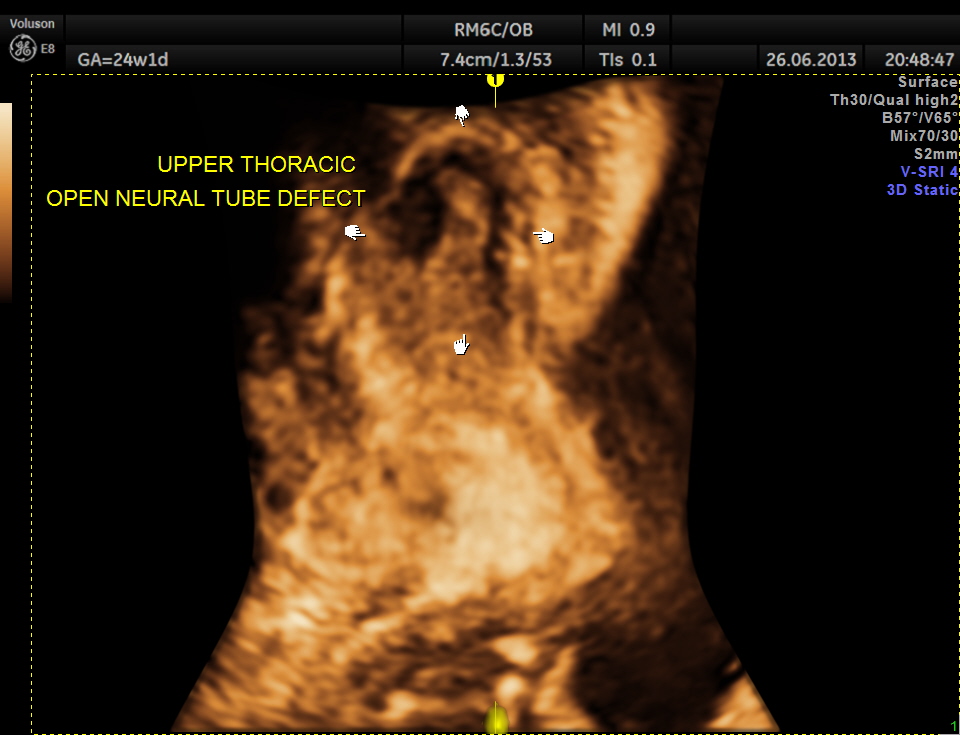

the following image shows the open neural tube defect at the same level as the heart.

moral of the case : a thorough examination of the spine is essential whenever a hydrocephalus is seen , especially with a distorted cerebellum.